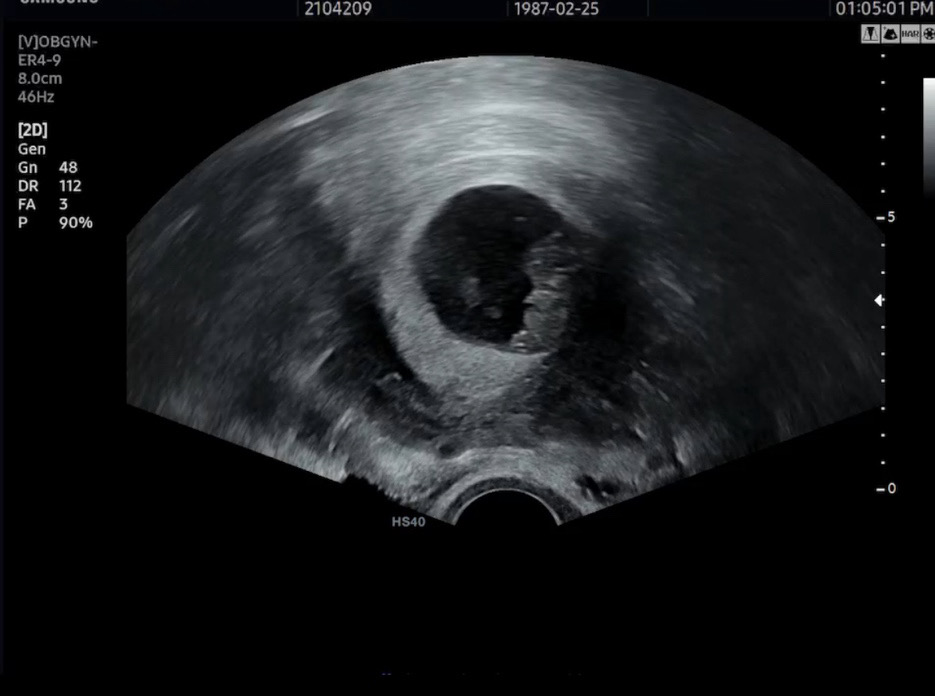

배볼록 애벌레 같기도 한 9주차 촘파 보고왔어요 꾸물꾸물 손 발 움직이는게 진짜 귀여운거 있죠 ㅜㅜ

저도 8주5일차에 가서 젤리곰 만나고 왔어요 너무 귀엽죠ㅜㅜ 그 쪼꼬만게 힘차게 움직이고 있다니 하나하나 더 조심하게 되는거같아요~